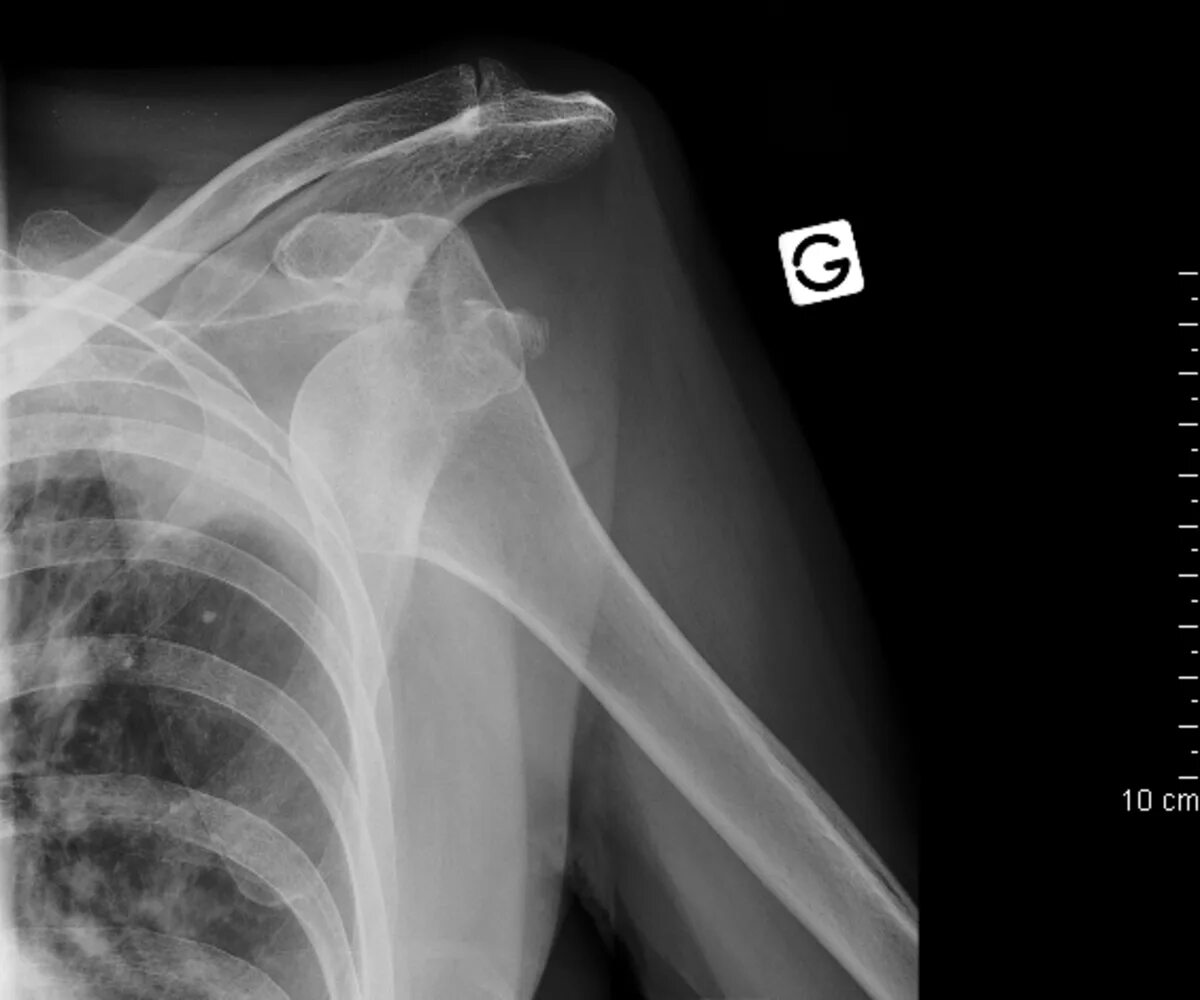

Нестабильность плечевого сустава мкб